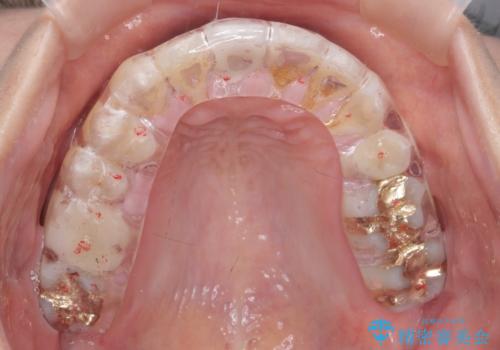

- 矯正や虫歯治療を終えた患者様です。

今後、詰め物や被せ物が歯軋りなどで割れないように、また歯のすり減りの防止のためナイトガードを作製しました。

ナイトガードは夜寝ている時に使用するものですがその時、矯正の後戻り防止の装置としても機能します。